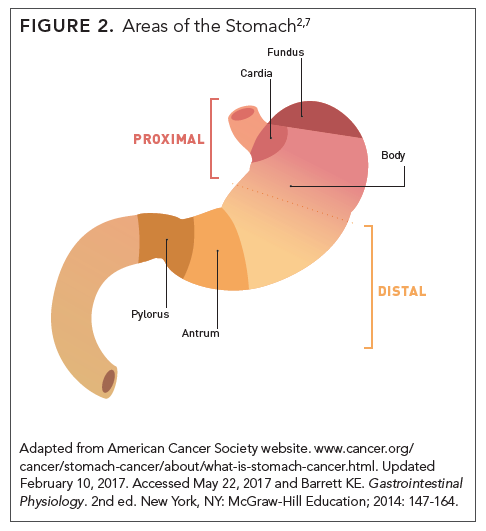

Stomach Cancer – Causes, Symptoms, Diagnosis and Treatment

Stomach Cancer | Symptoms, Causes, Stages, Treatment and Survival Rates

Stomach Cancer | Symptoms, Causes, Stages, Treatment and Survival Rates